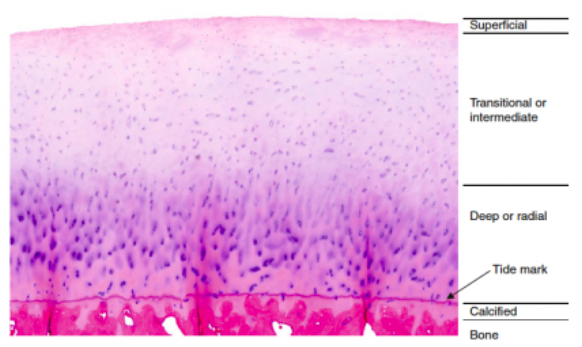

Cápas del cartílago

A

Superficial

Transcición

Profunda

- Línea de marea

Calcificada

Hueso